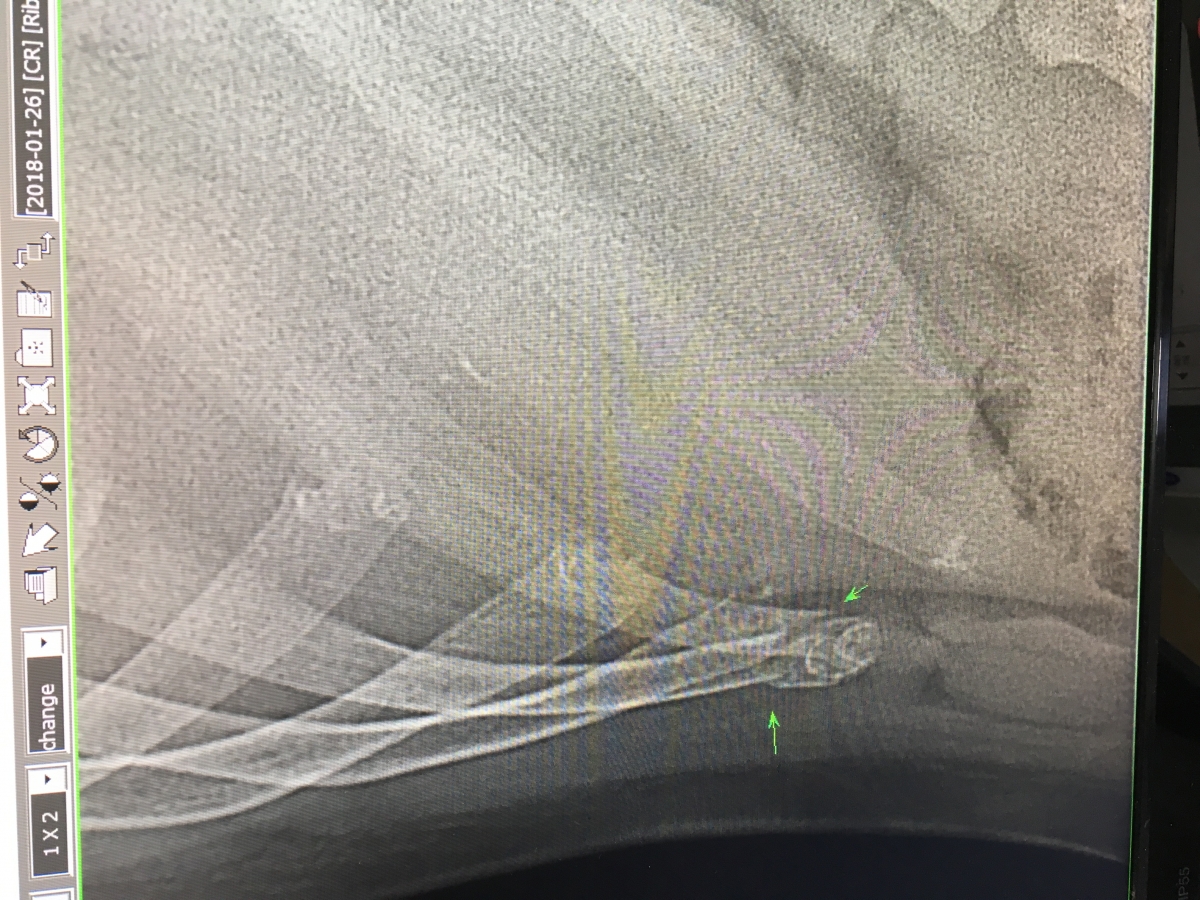

오늘 병원가서 다시 찍어봤는데, 잘보이네요 ㅋㅋ

의사선생님께서 두어달 이상 후에나 조금 차도가 있을거라니..

다행히 오른쪽 9,10번이고, 그나마 상태가 나쁘지 않아서..

다만.. 웃을때와 재채기할때 기분이 환상적인거 빼고는 괜찮습니다 ㅋㅋ